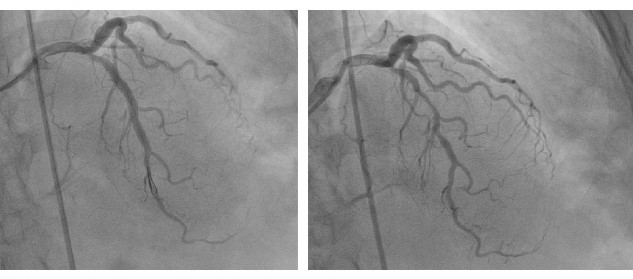

Una paciente de 80 años con antecedentes de diabetes mellitus tipo 2, hipertensión arterial, dislipidemia y cáncer de mama hace 6 años (con requerimiento de radioterapia) ingresó al hospital por dolor torácico de características típicas. En el examen físico se encontraron signos vitales estables, no hubo dificultad respiratoria ni tampoco signos de congestión pulmonar o sistémica. Se tomaron biomarcadores y un electrocardiograma, y los resultados fueron negativos para isquemia aguda. El ecocardiograma mostró fracción de eyección del ventrículo izquierdo (FEVI) conservada, dilatación auricular izquierda, ausencia de trastornos de la contractilidad e insuficiencia mitral leve a moderada. La coronariografía evidenció arteria coronaria izquierda sin lesiones obstructivas significativas, lesión calcificada del 70 % en el tercio proximal de la arteria descendente anterior y del 70 % de tercio medio de la misma arteria, coronaria derecha ocluida totalmente en su tercio medio, vaso severamente calcificado y oclusión total de la arteria posterolateral. Además, se realizó el diagnóstico de enfermedad coronaria multivaso; se solicitó la valoración por cirugía cardiovascular, que indicó que no había posibilidad de realizar el procedimiento quirúrgico por calcificación a lo largo de todas las arterias coronarias. Posteriormente, se llevó a cabo una coronariografía, donde se realizó la permeabilización de descendente anterior y posterior por medio de la AR e insertaron un estent medicado (Figura 1 y Figura 2). Durante el procedimiento, se reportó la microperforación de la arteria posterolateral, pero fue posible corregirla en el mismo tiempo quirúrgico con la técnica de embolización con micropartículas. Luego de la intervención, la paciente tuvo una adecuada evolución clínica y se dio su egreso.